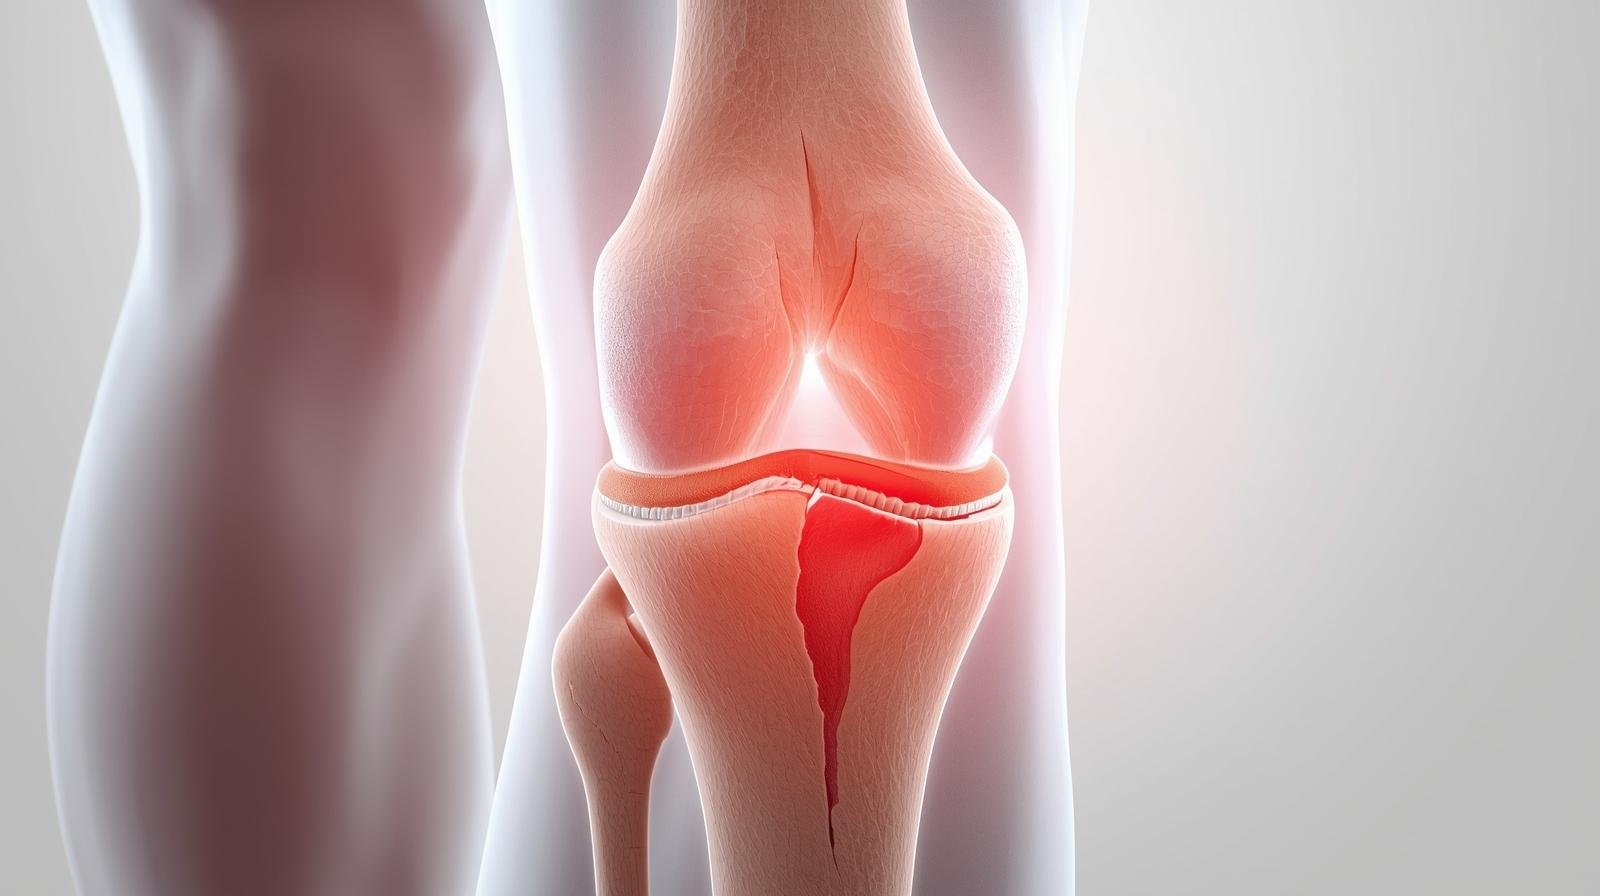

قد يكون ما تعاني منه هو تمزق الغضروف الهلالي… واحد من أكثر إصابات الركبة شيوعًا، سواء بين الرياضيين أو حتى الأشخاص العاديين.

في البداية، يجب أن نعرف أن الغضروف الهلالي هو نسيج مرن يقع بين عظام الركبة. ووظيفته الأساسية هي امتصاص الصدمات وتقليل الاحتكاك. لذلك، عندما يحدث تمزق غضروف الركبة، تتأثر الحركة الطبيعية للمفصل بشكل واضح.

بمعنى آخر، تخيل أن الغضروف هو الوسادة التي تحمي العظام من الاحتكاك المباشر. فإذا تمزقت هذه الوسادة، يبدأ الألم ويزداد الاحتكاك تدريجيًا.

أهمية الغضروف داخل مفصل الركبة

من ناحية أخرى، يلعب الغضروف دورًا أساسيًا في: